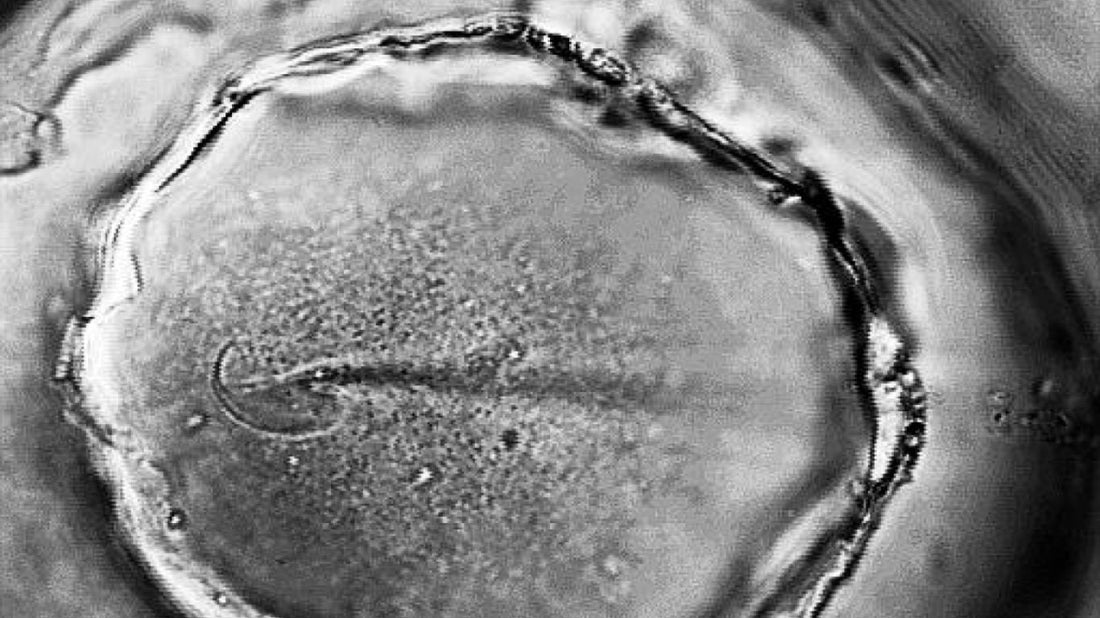

Qu’est ce que l’ovulation ? L’ovulation est la libération d’un ovocyte mature par l’un des deux ovaires généralement autour du 14ème jour quand le cycle est de 28 jours. L’ovulation est le moment le plus fertile du cycle : l’ovocyte peut être fécondé jusqu’à 24h après sa libération. Une ovulation bien réglée est indispensable pour une conception naturelle. L’ovulation est régulée par un équilibre hormonal très précis qui implique : la FSH (hormone folliculo-stimulante) : elle stimule le développement des follicules l’oestradiol : produite par les follicules en croissance pour préparer l’endomètre et une glaire optimale pour la remontée des spermatozoïdes. le pic de LH (hormone lutéinisante) déclenche la libération de l’ovocyte mature. Après l’ovulation, le follicule rompu devient le corps jaune qui sécrète la progestérone essentielle à la nidation en cas de fécondation. Quelles peuvent être les causes des problèmes d’ovulation ? Certaines femmes n’ovulent pas régulièrement ou pas du tout. Les causes les plus fréquentes sont : le SOPK (Syndrome des Ovaires Polykystiques) l’IOP (Insuffisance Ovarienne Précoce) les déséquilibres thyroïdiens une alimentation carencée la pratique d’un sport intense un poids trop faible (voire antécédent d’anorexie) le surpoids le stress chronique Comment peut-on améliorer son ovulation ? Certains nutriments peuvent jouer un rôle important dans la régulation hormonale et qualité de l’ovulation, c’est le cas : du myo-inositol : pour restaurer l’ovulation des folates : pour soutenir la croissance folliculaire et l’ovulation du Zinc et de la vitamine D : pour la régulation hormonale et la fonction ovarienne De plus, une alimentation équilibrée riche en légumes et en bonnes graisses peut contribuer à stabiliser le cycle, restaurer l’ovulation et favoriser la fertilité.

Comment définit-on une bonne qualité ovocytaire ? La qualité ovocytaire désigne la capacité d’un ovocyte (ou ovule) à être fécondé, à se diviser correctement et à donner un embryon viable. C’est l’un des facteurs clés de la fertilité féminine au même titre que l’ovulation ou la réserve ovarienne. Un ovocyte de bonne qualité possède un matériel génétique intègre, une bonne fonction mitochondriale, un équilibre oxydatif optimal ce qui lui confère la capacité de développer en embryon sain. La qualité ovocytaire dépend de plusieurs paramètres : l’âge : → La qualité ovocytaire diminue progressivement à partir de 35 ans. le stress oxydatif : → Les radicaux libres endommagent l’ADN ovocytaire. l’état inflammatoire chronique : → La présence de pathologie comme l’endométriose, le SOPK.. les troubles métaboliques : → L’insulinorésistance (SOPK), les carences nutritionnelles. l’environnement → L’exposition à des perturbateurs endocriniens, la pollution, la consommation de tabac, d’alcool, de drogues.. → La qualité du sommeil, du microbiote intestinal et la gestion du stress. On ne peut pas créer de nouveaux ovocytes mais on peut améliorer leur développement pendant les 3 mois qui précèdent l’ovulation. C’est durant cette phase de maturation folliculaire que les ovocytes sont les plus sensibles aux apports nutritionnels, hormonaux et environnementaux. Comment peut-on améliorer la qualité ovocytaire ? Pour soutenir la qualité ovocytaires il existe plusieurs solutions : une supplémentation en myo-inositol (pour l’équilibre hormonal), en Folates (avec de la vitamine B9 active!), en vitamine B12, en Zinc, en iode, en vitamine D et en antioxydants (telle que la vitamine E ou la vitamine C) la gestion du stress un sommeil réparateur une activité physique douce (yoga, pilates, marche, natation… ) une réduction de l’exposition aux toxiques (tabac, alcool, drogues…)

Une grossesse sur 20 (soit environ 5% des grossesses en France) en France est issue d’une PMA. La procréation médicalement assistée que l’on retrouve parfois sous le terme AMP Assistance Médicale à la Procréation est un ensemble de techniques venant en aide aux couples qui connaissent des difficultés à concevoir un enfant. Elle regroupe plusieurs techniques allant de la stimulation ovarienne à l'insémination artificielle. La PMA ne traite pas la cause de l’infertilité, mais accompagne les couples en les aidant à contourner les obstacles à la fécondation naturelle. Quelles sont les différentes solutions proposées dans un parcours PMA ? La PMA a fait d'immenses progrès ces dernières années et une batterie de solutions ciblées sont disponibles : la Stimulation Ovarienne (IS) : c’est une technique médicale qui va déclencher le développement des follicules ovariens afin de favoriser l’ovulation. l'Insémination Intra Utérine (IIU) : il s’agit de déposer le sperme directement dans l’utérus au moment de l’ovulation. Cette méthode est pratiquée en cas de troubles de l’ovulation chez la femme ou dans les cas de spermogrammes légèrement altérés chez l’homme. la Fécondation In Vitro (FIV) : les ovocytes et les spermatozoïdes sont mis en fécondation en laboratoire. Puis une fois la fécondation réussie, l’embryon se développe en laboratoire puis est transféré dans l'utérus ou congelé. Cette méthode est réalisée : en cas d’échec de l’insémination intra utérine, de pathologie des trompes qui peuvent être obstruées ou absentes de pathologies détectées comme le SOPK ou l’endométriose, d’anomalies des spermatozoïdes chez l’homme, en fonction de l’âge. la FIV ICSI (Fécondation In Vitro en anglais « Intra Cytoplasmic Sperm Injection »). Il s’agit d’une micro injection d’un seul spermatozoïde dans l'ovocyte. Cette méthode est pratiquée en cas d’infertilité masculine sévère et d’échec de la fécondation. le don de gamètes : c’est l’utilisation d’ovocytes ou de spermatozoïdes d’un donneur en cas de réserve ovarienne basse, d’absence de partenaire masculin. la congélation ovocytaire. C’est la préservation de la fertilité pour “plus tard”. Il s’agit de réaliser une stimulation ovarienne afin de produire un maximum d'ovocytes de bonne qualité qui seront congelés et utilisés au moment voulu. (mettre lien de la page nos missions) la congélation embryonnaire. Lors d’une fécondation in vitro, plusieurs embryons peuvent être obtenus. Afin d’éviter les grossesses multiples, un seul embryon est transféré. Ceux restants, dits surnuméraires, sont congelés ou plus précisément “vitrifiés”. Cette technique permet de donner des chances supplémentaires au couple pour leur premier enfant. En cas de grossesse, ces embryons pourront servir lors du désir d’un futur enfant, sans avoir à réaliser une nouvelle ponction folliculaire. Quelles sont les étapes clés d’un parcours PMA ? 1. Le bilan de fertilité complet Avant toute prise en charge, un diagnostic précis est réalisé pour évaluer la fertilité du couple. Cela inclut des analyses hormonales, une échographie pelvienne, et un spermogramme. 2. La stimulation ovarienne Selon la technique envisagée, la stimulation peut prendre différentes formes : - Stimulation simple : utilisée pour favoriser l’ovulation dans le cadre de rapports programmés ou d’une insémination intra-utérine (IIU). - Stimulation multifolliculaire : pratiquée pour développer plusieurs follicules en vue d’une ponction ovocytaire dans le cadre d’une Fécondation In Vitro (FIV). 3. Le suivi médical de la stimulation Pendant la stimulation, un suivi échographique et hormonal régulier permet d’ajuster le traitement et de déterminer le moment optimal pour l’intervention. 4. La tentative de conception En fonction du protocole choisi : - Rapports ciblés - Insémination intra-utérine (IIU) - Fécondation in vitro (FIV) avec ponction des ovocytes et mise en fécondation en laboratoire 5. Le transfert embryonnaire et la nidation En cas de FIV, l'embryon est directement transféré dans l’utérus. La nidation (implantation de l’embryon) est ensuite espérée dans les jours qui suivent le rapport, l'IIU ou le transfert embryonnaire (FIV) Même dans un cadre médicalisé, certaines solutions naturelles bien formulées et hautement dosées peuvent améliorer la réussite de la PMA. C’est le cas des compléments alimentaires ciblés qui peuvent optimiser la qualité des ovocytes, protéger les cellules reproductives, réduire l’inflammation, soutenir l’équilibre hormonal, réduire le stress.